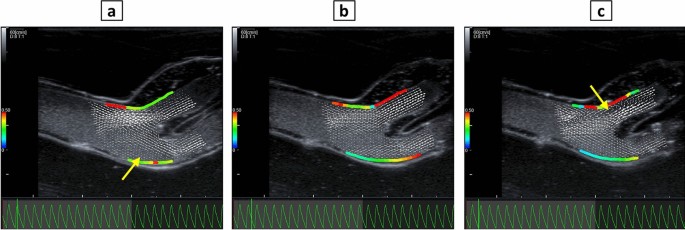

An ultrasound system (Lisendo 880, FujiFilm, Tokyo, Japan) equipped with vector flow mapping (VFM) function was used for evaluation of fluid dynamics on the longitudinal plane of the vessel model, encompassing CCA, ICA, and ECA. To evaluate the velocity vectors and WSS at specific points in the cardiac cycle, the pressure sensor voltage output (0–10 V) was adapted to the input voltage of the built-in ECG device of the ultrasound system (0–5 mV). The vessel model was subjected to pulsatile flow condition during the experiments, which lasted approximately 20 min.

Feasibility of fluid dynamics assessment

The velocity vectors at PVA-H carotid artery bifurcation during 15 pulsation cycles are depicted in Supplementary Video S1. Three frames of this video are selected and shown in Fig. 11. The Fig. 11a demonstrates the velocity vectors at peak systolic pressure, depicting a recirculation zone at carotid bulb. A second recirculation zone occurred at the end of diastole, shortly before the beginning of the systolic phase at the carotid bulb proximal to ICA, as shown in Fig. 11c. The absolute values of WSS over the all cycle ranged between 0.1 and 0.6 Pa on the outer wall of ICA adjacent to stenosis, with the maximum WSS occurring during diastole presumably due to pressure-flow waveform shift as previously shown30.

The feasibility of ultrasound-based in vitro assessment of fluid dynamics under pulsatile flow was demonstrated in this study. In a previous clinical study, fluid dynamics at carotid bifurcation of eight volunteers was assessed in longitudinal plane with vector flow ultrasound50. A vortex with complex flow in carotid bulb in all the volunteers in different phases of the cardiac cycle was shown, comparable to the qualitative assessment of flow vectors performed in our study. The range of WSS values observed in PVA-H model is consistent with findings from a clinical study involving 20 patients, where WSS was indicated as 0.72 ± 0.30 Pa in ICAs51. In our investigation, we found that the peak wall shear stress (WSS) in ICAs did not coincide with the peak systolic pressure. This observation is also consistent with the findings of Wang et al., who highlighted the significance of the phase shift between pressure and WSS and proposed it to play a crucial role in identifying areas prone to atherosclerosis within the carotid artery30.